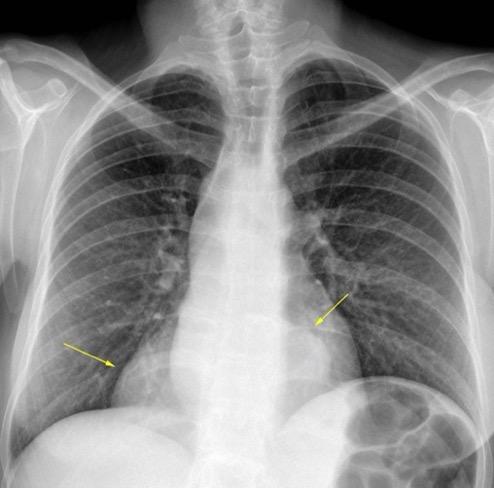

Triada de Garland

Ganglios paratraqueales derechos e hiliares bilaterales

95% de pacientes tienen ganglios hiliares bilaterales aislados o con afectación mediastínica (espec. paratraqueal derecho).

Criado E et al. Pulmonary sarcoidosis: typical and atypical manifestations at high-resolution CT with pathologic correlation. Radiographics. 2010